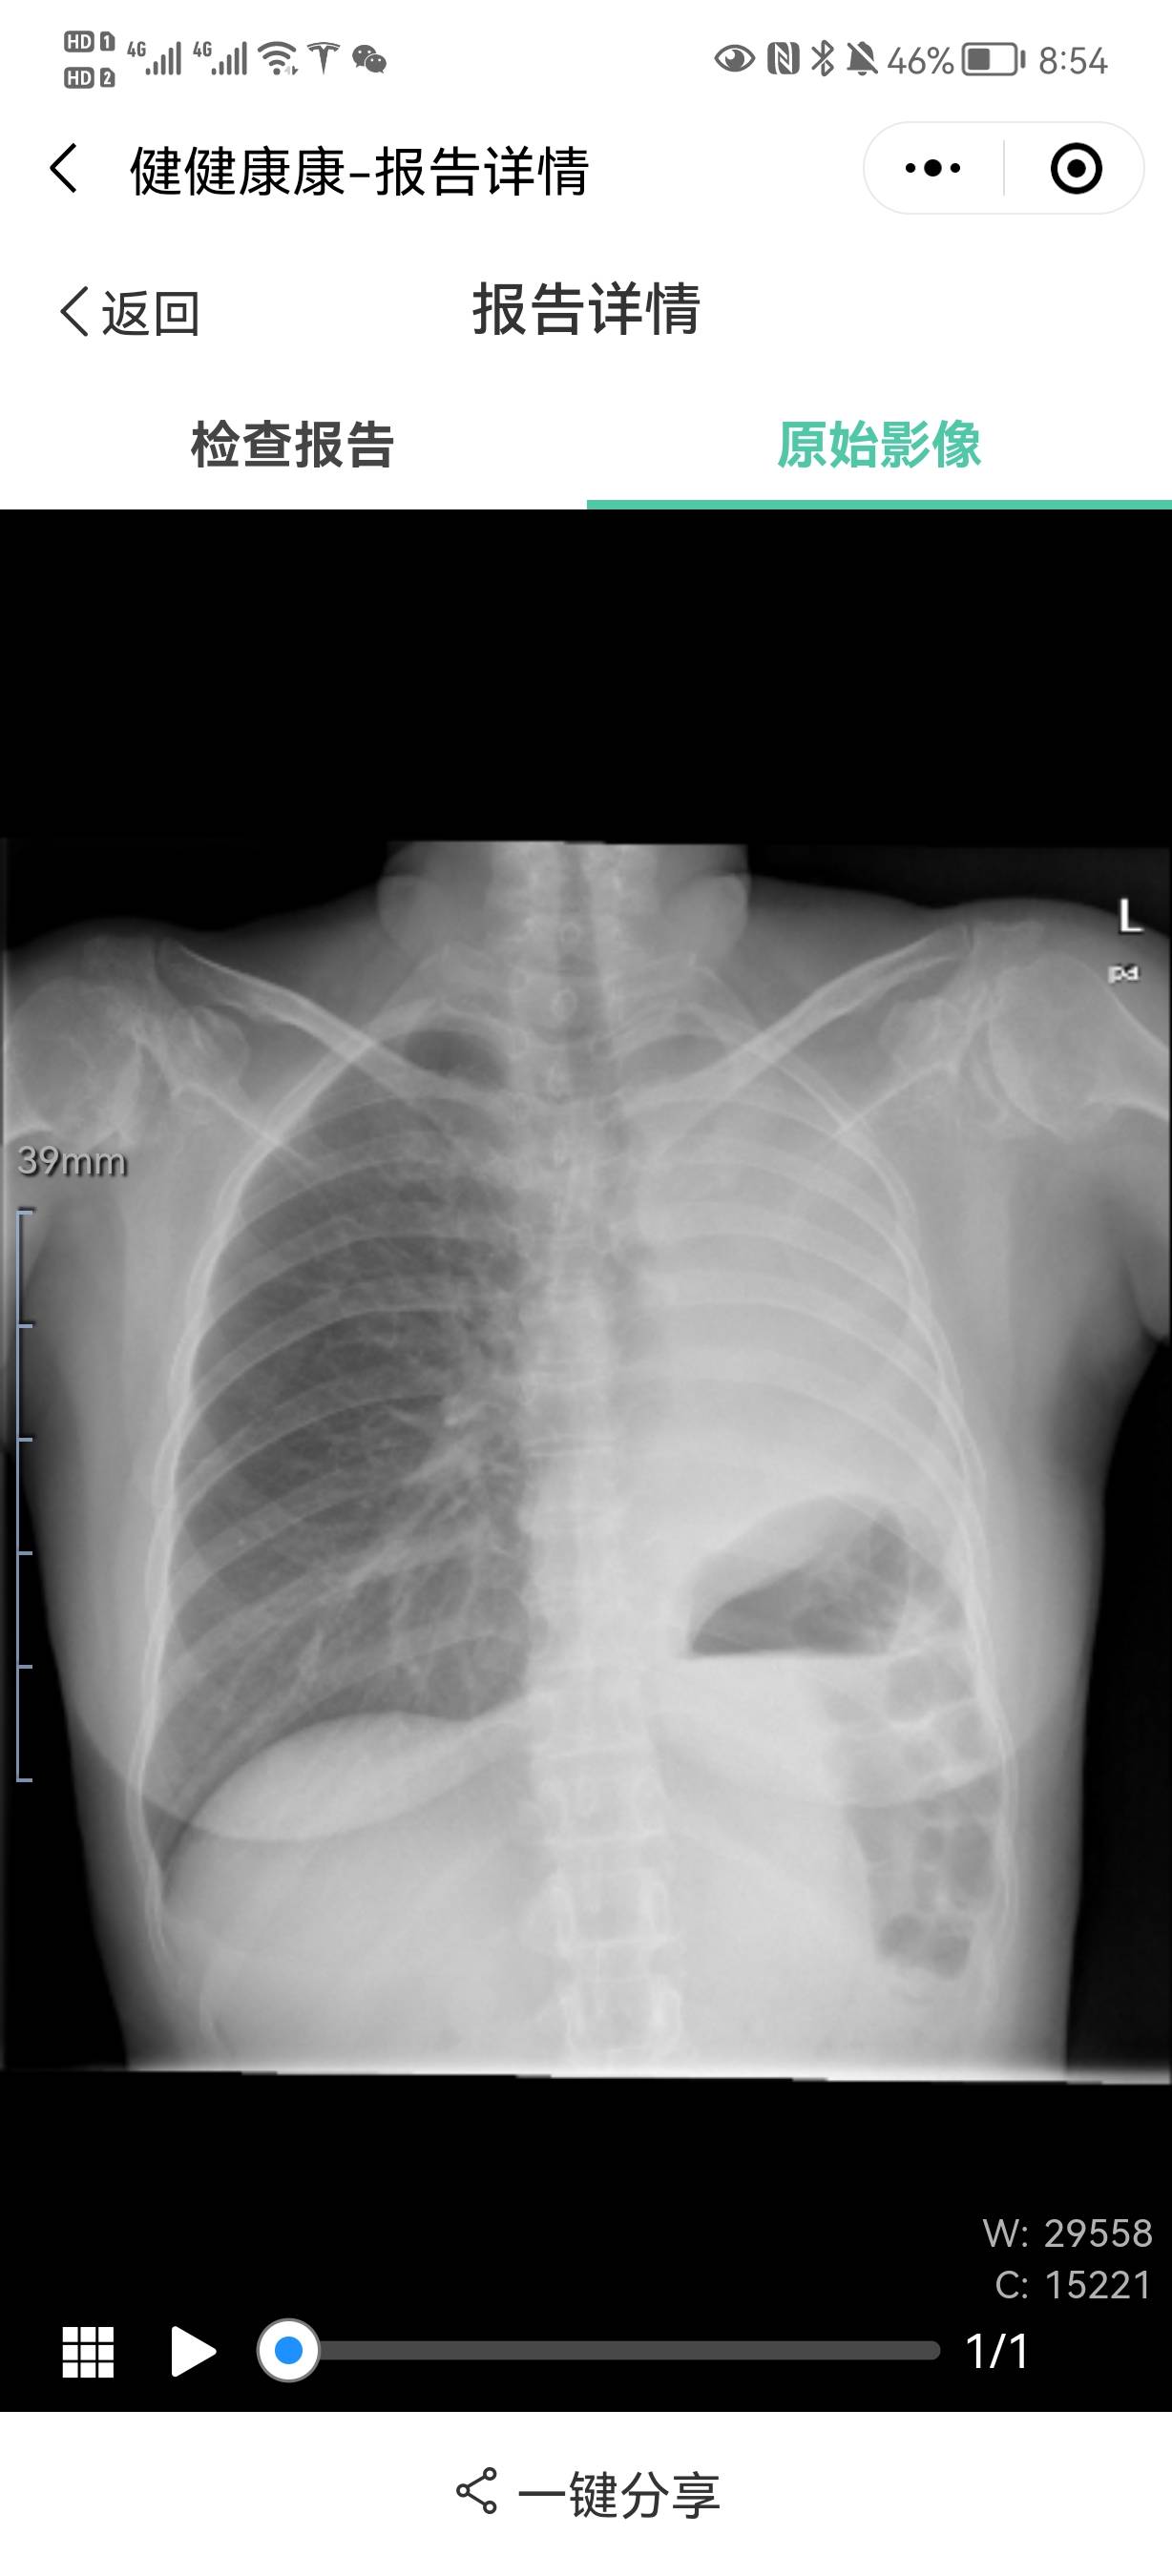

如果是没有胸闷、气喘、呼吸困难等情况出现,可以不用引流,让胸水慢慢吸收,时间相对较慢。